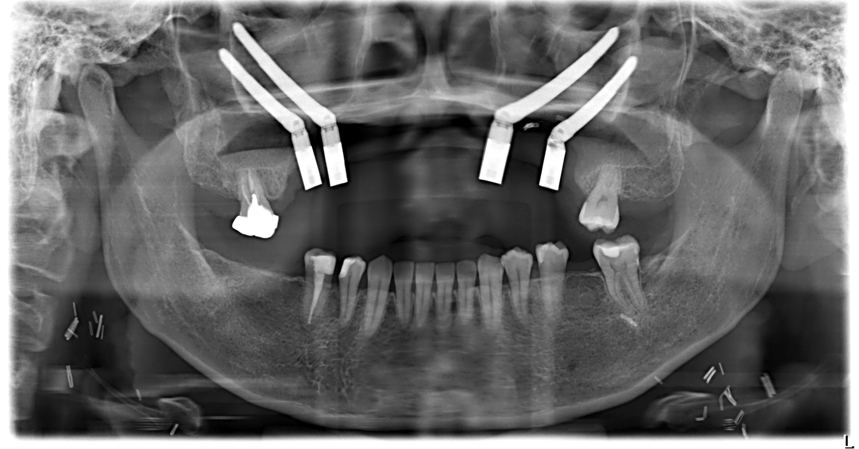

收治病例的中山醫學大學附設醫院口腔顎面外科團隊,採用先進的「電腦數位模擬整合手術」為許小姐尋求生機。在手術前,由中山附醫口腔顎面外科主治醫師邱昱瑋、陳怡孜及陳珮吟組成的醫療團隊,先利用電腦斷層掃描資料,在虛擬環境中精準規劃腫瘤切除的範圍,確保徹底清除癌細胞。

團隊也模擬了因上顎骨大量缺損,將植體植入顴骨中;手術當天,團隊結合了術前規劃的3D列印切割導引板與即時電腦導航系統,在一次性的手術中,精準完成上顎口腔癌腫瘤切除、頸部淋巴廓清、取用自體組織的游離皮瓣重建,以及高難度的顴骨植牙等四大關鍵程序。